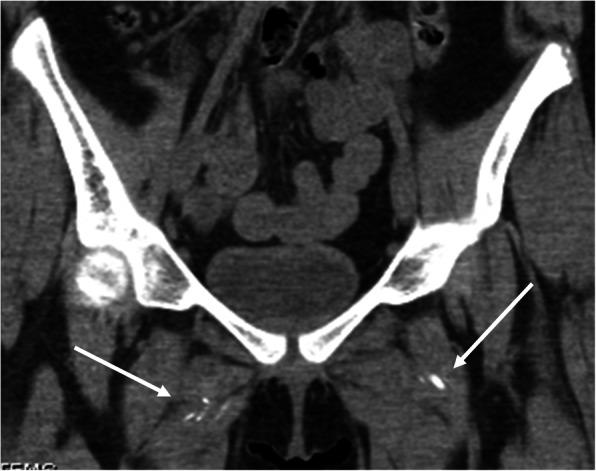

We describe the case of a 13 year-old girl with overlap syndrome with features of juvenile dermatomyositis and systemic lupus erythematosus. After 22 months of extensive immunosuppressive therapy, including monthly IVIG and Rituximab, she continued to have pain and weakness of the lower extremities. A CT scan was performed which showed significant multifocal soft tissue calcifications of the pelvis. She was started on treatment with oral alendronate with the goal of improving her calcinosis and improving her symptoms. After several months of therapy, our patient reported subjective improvement of her lower extremity pain and weakness, as well as complete resolution of abnormalities previously seen on physical examination. A repeat CT scan of the pelvis was performed after 11 months of therapy and demonstrated complete resolution of the previously seen calcinosis.

我们描述了一名13岁女孩的病例,她患有重叠综合征,具有幼年皮肌炎和系统性红斑狼疮的特征。在进行了22个月的广泛免疫抑制治疗后,包括每月静脉注射免疫球蛋白和利妥昔单抗,她的下肢仍持续疼痛和无力。进行了CT扫描,结果显示骨盆有明显的多灶性软组织钙化。她开始接受口服阿仑膦酸钠治疗,目的是改善她的皮肤钙化并缓解症状。经过几个月的治疗,我们的患者报告下肢疼痛和无力主观上有所改善,并且之前体格检查中发现的异常完全消失。治疗11个月后对骨盆进行了重复CT扫描,结果显示之前所见的皮肤钙化完全消失。